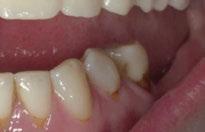

Para ilustrar el proceso, presentamos el caso de una mujer joven diagnosticada de carcinoma adenoide quístico en la región posterior del hemipaladar izquierdo (Figuras 1 y 2). El procedimiento quirúrgico realizado fue una

Figura 1. Imagen preoperatoria de la paciente.

Figura 2. Carcinoma adenoide quístico en región posterior del hemimaxilar izquierdo.